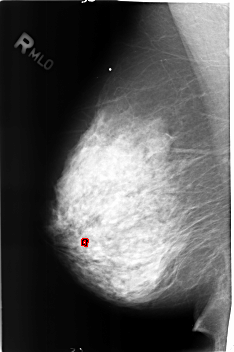

B_3175_1.RIGHT_MLO

RIGHT_MLO LINES 4568 PIXELS_PER_LINE 3032 BITS_PER_PIXEL 12 RESOLUTION 50 OVERLAY

FILE: B_3175_1.RIGHT_MLO.OVERLAY

TOTAL_ABNORMALITIES 1

ABNORMALITY 1

LESION_TYPE CALCIFICATION TYPE LUCENT_CENTER DISTRIBUTION N/A

ASSESSMENT 2

SUBTLETY 3

PATHOLOGY BENIGN_WITHOUT_CALLBACK

TOTAL_OUTLINES 1

BOUNDARY